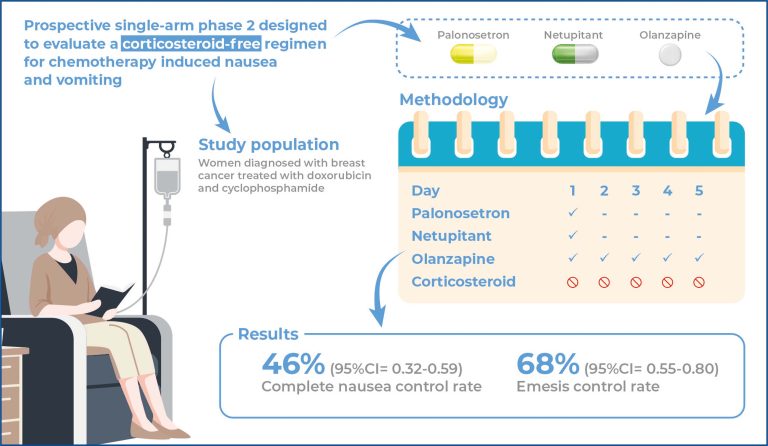

Omission of dexamethasone in prophylaxis for highly emetogenic chemotherapy in patients with breast cancer

DOI: 10.31744/einstein_journal/2025AO1124

Highlights ■ Evaluation of a corticosteroid-free antiemetic regimen. ■ Primary endpoint: 46% nausea control. ■ Secondary endpoint: 68% emesis control. ■ Comparable to standard four-drug protocols. ABSTRACT Objective: Chemotherapy-induced nausea and vomiting are highly prevalent adverse events that can lead to poor treatment adherence and a decreased quality of life. To the best of our knowledge, the complete omission of dexamethasone from any regimen for preventing nausea and vomiting has not yet been evaluated. This study aimed to evaluate the […]

Keywords: Antineoplastic agents; Breast neoplasms; Dexamethasone; Drug therapy; Drug-related side effects and adverse reactions; Nausea; Olanzapine; Vomiting